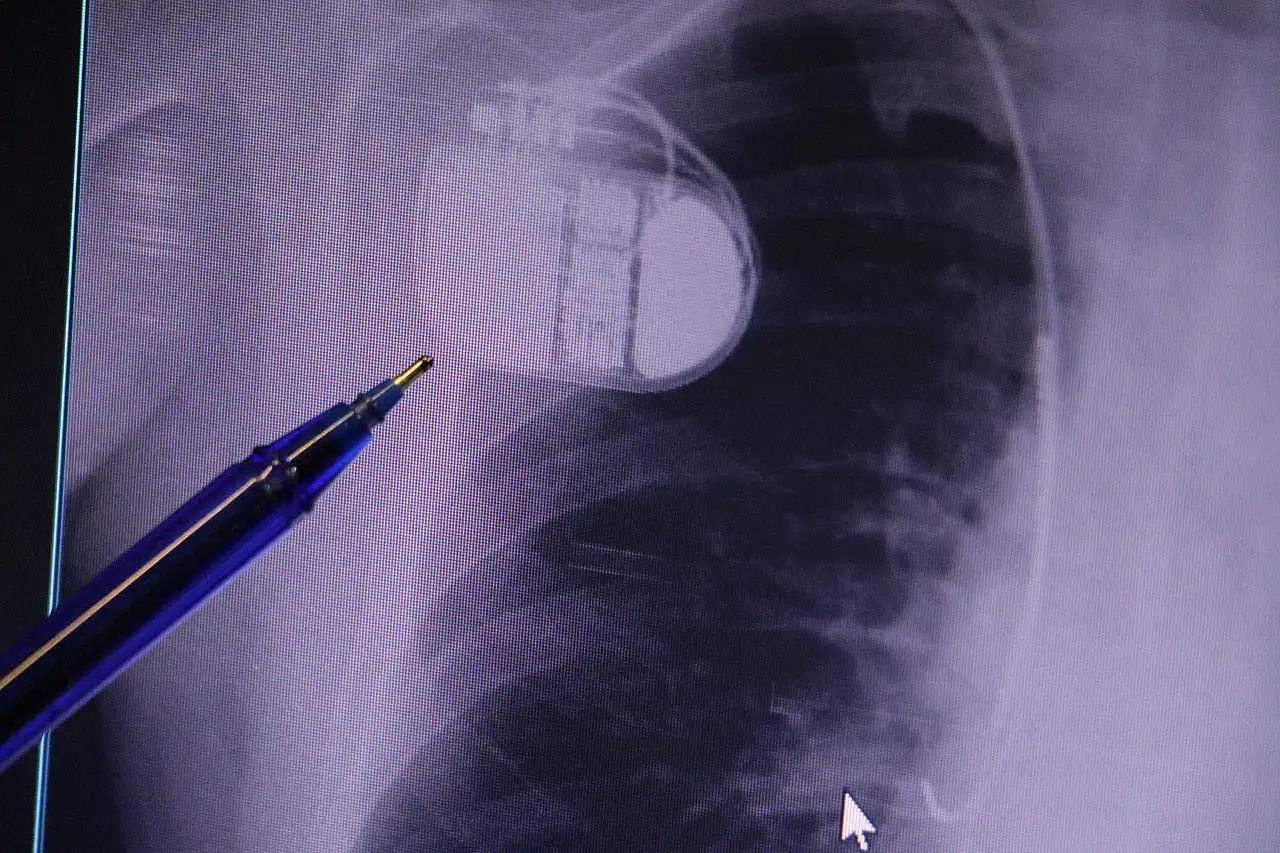

Konuya ilişkin açıklamalarda bulunan Kardiyoloji Bölümü Uzmanı Dr. İsmail Erdoğu, kalp pilinin önemine vurgu yaptı. Erdoğu, Yeni nesil kalp pillerinin MR cihazlarına girmeye imkan sağladığı, ancak tarama cihazlarından geçmenin önerilmediğini ifade ederek, "Soğuk hava nedeniyle oluşan titremeler, kalp pilinin kalbin durduğunu sanmasına ve yanlış şoklamaya yol açabilir. Bu nedenle hastalarımızın bu dönemlerde daha dikkatli olmalarını öneriyoruz" dedi.

Kalp pilleri ile MR cihazına girilebileceğini belirten Erdoğu, "Çok büyük bir ameliyat değil ama yine de ciddi bir cerrahi işlem. Kalp pili, tıpta son 30 yılda yaşanan gelişmelerden en büyüğü. Bir bilgisayarın küçültülüp insan vücuduna konulmuş hali aslında. İnsan ömrünü ciddi oranda uzatan bir tedavi. İnsanlar bir şokla hayata tutunurken, pil olmasaydı öleceğini düşündüğümüz birçok hastamız var. Kalp pilinin bu özelliği, uygun hastalarda ciddi oranda ani ölümü engelliyor. Hastanın başına gelecek bir kalp durması durumunda yanında bir sağlıkçı yoksa, onun ritmini düzeltecek defibrilatör cihazı yoksa hastayı hayatta tutmak mümkün değil. Uygun endikasyonlarda kalp pili olduğu zaman, pil hastaların ritmini algılıyor ve acilde yapılan şoklamayı yaparak hastayı hayata döndürüyor. Kalp pillerinde yeni teknolojilerle MR'a girmek mümkün, tomografiye zaten girebiliyorlar. Tarama cihazlarından geçmelerini uygun görmüyoruz. Bu tarz durumlarda hastalarımız 'kalp pilim var' dediğinde muaf tutuluyorlar. Kalp pilleri ciddi teknolojik cihazlardır. Vücudun içindeki titreşimi, örneğin mikser kullanmak, kolunu sallayacak herhangi bir eylem kalp pilinde olumsuz etki oluşturabilir. Soğuk havalarda vücutta oluşan ciddi titremeler kalp pilinin hafızasını karıştırıp kalbin durduğunu düşündürebilir ve gereksiz şoklama yapabilir. Bu tarz kişilerin soğuk havalarda daha temkinli olması gerekir" diye konuştu.